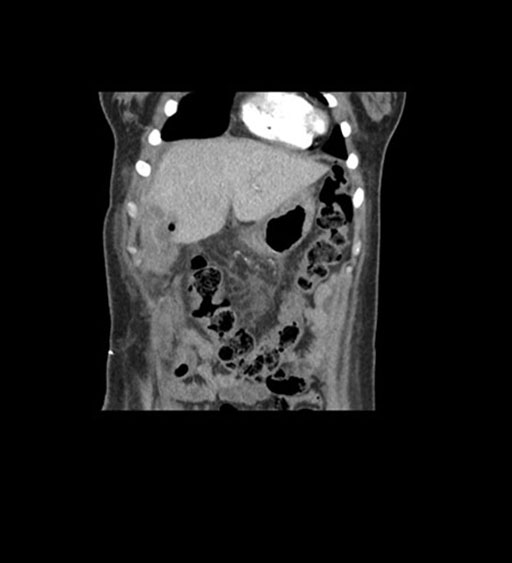

Imaging Analysis

Look through the patient's CT scan to identify any areas of concern for the necessary procedure.

Coronal Venous

Based on initial findings, which issue(s) would you be most concerned about?